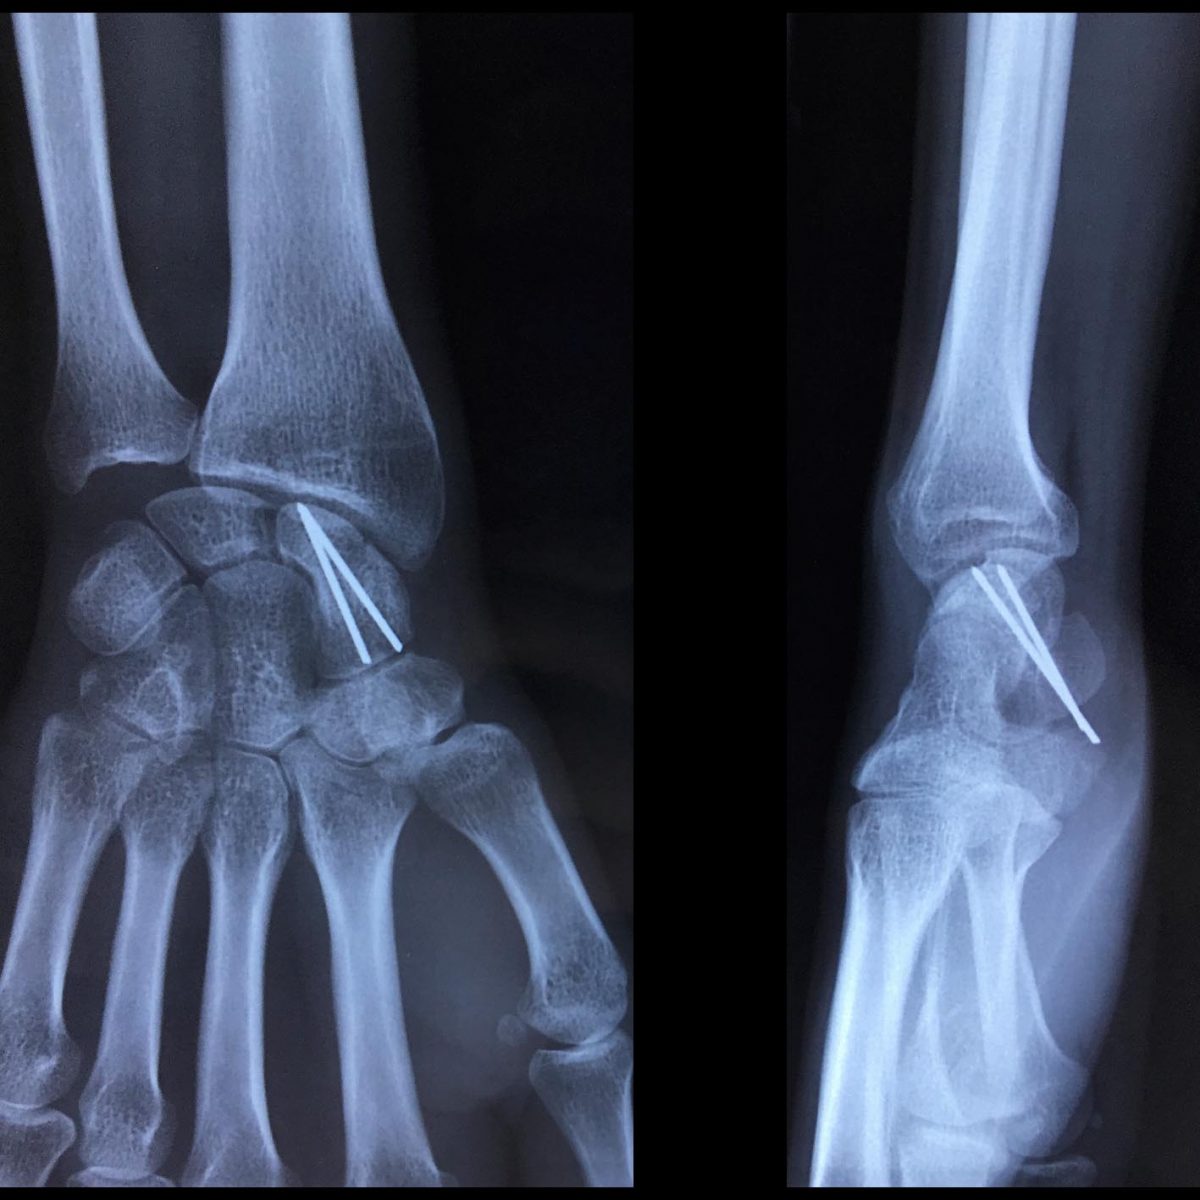

Fracture Scaphoïde Temps De Guérison . Fracture du crâne temps de guérison ? Conseils kiné La fracture du scaphoïde est une blessure fréquente, surtout chez les amateurs de sports ou lors d'accidents de la vie quotidienne Le scaphoïde est l'un des 8 os constitutifs du carpe, à la base du poignet, et ses fractures sont extrêmement fréquentes

Fractures scaphoïde, main Dr Pelissier Chirurgien orthopédiste et traumatologue from maxime-pelissier.fr

Source: elarteewv.pages.dev Prise en charge de la fracture du scaphoïde , Si la fracture du scaphoïde n'est pas déplacée (l'os ne s'est pas déplacé au niveau de la fracture), elle peut généralement être traitée avec succès par un plâtre La fracture du scaphoïde est une blessure fréquente, surtout chez les amateurs de sports ou lors d'accidents de la vie quotidienne

Source: ladagalba.pages.dev Fracture scaphoïde diagnostic, durée, rééducation et guérison , Une fracture scaphoïde non déplacée, c'est-à-dire sans diastasis interfragmentaire, nécessite un temps de guérison moindre que dans le cas d'un déplacement ou d'une fracture du pôle proximal impliquant une chirurgie Qu'est-ce qu'une fracture du scaphoïde ? Le poignet est composé de huit osselets regroupés en deux rangées distinctes